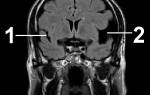

- Ультразвуковое сканирование вен нижних конечностей — определяет наличие тромбов и место их локализации.

- Дуплексное сканирование кровеносной системы — современный метод диагностики, работающий по типу УЗИ, но с расширенными возможностями (определения скорости кровотока, глубины патологии).

- Компьютерная томограмма — проводится для выявления злокачественных новообразований в организме.